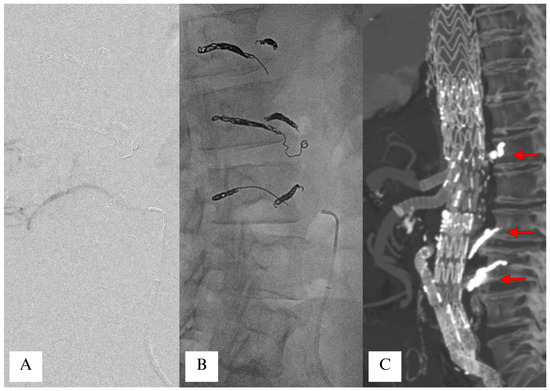

- Etz, C.D.; Debus, E.S.; Mohr, F.W.; Kölbel, T. First-in-man endovascular preconditioning of the paraspinal collateral network by segmental artery coil embolization to prevent ischemic spinal cord injury. J. Thorac. Cardiovasc. Surg. 2015, 149, 1074–1079. [Google Scholar] [CrossRef] [PubMed]

- Petroff, D.; Czerny, M.; Kölbel, T.; Melissano, G.; Lonn, L.; Haunschild, J.; von Aspern, K.; Neuhaus, P.; Pelz, J.; Epstein, D.M.; et al. Paraplegia prevention in aortic aneurysm repair by thoracoabdominal staging with ‘minimally invasive staged segmental artery coil embolisation’ (MIS2ACE): Trial protocol for a randomised controlled multicentre trial. BMJ Open 2019, 9, e025488. [Google Scholar] [CrossRef]

- Branzan, D.; Etz, C.D.; Moche, M.; Von Aspern, K.; Staab, H.; Fuchs, J.; Bergh, F.T.; Scheinert, D.; Schmidt, A. Ischaemic preconditioning of the spinal cord to prevent spinal cord ischaemia during endovascular repair of thoracoabdominal aortic aneurysm: First clinical experience. EuroIntervention 2018, 14, 828–835. [Google Scholar] [CrossRef]

- Addas, J.A.K.; Mafeld, S.; Mahmood, D.N.; Sidhu, A.; Ouzounian, M.; Lindsay, T.F.; Tan, K.T. Minimally Invasive Segmental Artery Coil Embolization (MISACE) Prior to Endovascular Thoracoabdominal Aortic Aneurysm Repair. Cardiovasc. Interv. Radiol. 2022, 45, 1462–1469. [Google Scholar] [CrossRef]

- Haunschild, J.; Köbel, T.; Misfeld, M.; Etz, C.D. Minimally invasive staged segmental artery coil embolization (MIS2ACE) for spinal cord protection. Ann. Cardiothorac. Surg. 2023, 12, 492–499. [Google Scholar] [CrossRef]

- Dabravolskaite, V.; Xourgia, E.; Kotelis, D.; Makaloski, V. The Safety and Outcome of Minimally Invasive Staged Segmental Artery Coil Embolization (MIS2ACE) Prior Thoracoabdominal Aortic Aneurysm Repair: A Single-Center Study, Systematic Review, and Meta-Analysis. J. Clin. Med. 2024, 13, 1408. [Google Scholar] [CrossRef] [PubMed]

- Branzan, D.; Geisler, A.; Steiner, S.; Scheinert, D.; Funk, K.; Schmidt, A. Endovascular occlusion of segmental arteries feeding the anterior spinal artery to stage endovascular thoracoabdominal aortic repair. JTCVS Open 2024, 18, 1–8. [Google Scholar] [CrossRef] [PubMed]